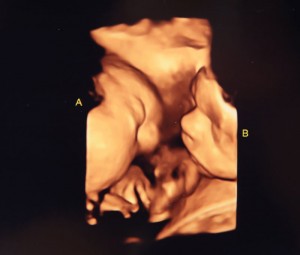

You can find many ultrasound videos of babies dancing in utero.

Barberic reports she’s seen kicks that look like dancing, especially with twins.

“I’ve seen legs moving, kicking and head flung back,” she said.

Researchers support these observations, reporting that at 21 weeks there is full kicking – somewhat like martial arts.

An Irish study revealed that babies move in reaction to sound as early as 16 weeks. This was earlier than previous estimates and before completion of the ear development, suggesting there is more to hearing than the ear alone.